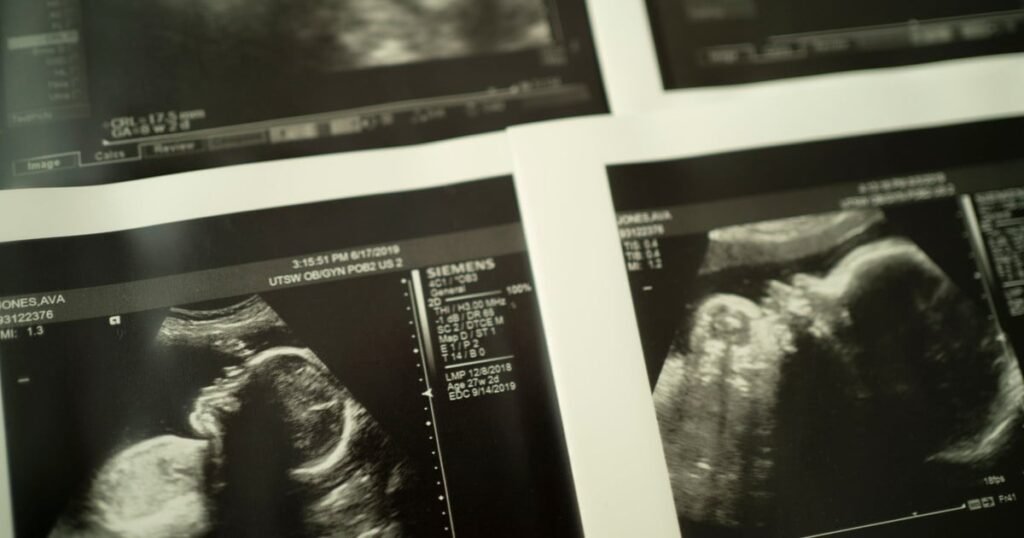

Teams plan to meet on Friday for the first time to discuss possible research goals. These include: understanding why some placenta does not get, and the fruits do not grow properly; assessment of fetal decline; Considering the best times for delivery and use of advanced technologies to learn how blood tests, biomarkers and ultrasound can help predict the stillborn. They can also evaluate how electronic medical documents and artificial intelligence can help doctors and nurses identify early signs of the risk of stillbirths. While the announcement was not mentioned racial disproportionsA spokesman said the consortium hopes to determine the factors that determine who is more at risk of having a stillborn.